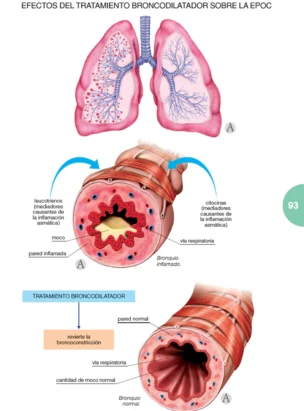

EPOC

Un libro de la extensión de este no puede explicarlo todo sobre el tema. Pero sí aporta una cantidad más que suficiente de información para que tanto el profesional, como el paciente puedan encontrar en él todo aquello que constituye el núcleo fundamental de conocimientos sobre la enfermedad, además de un gran acopio de materiales complementarios, tanto de tipo ilustrativo como, sobre todo, práctico, que servirán eficientemente para conocer en su globalidad qué es la EPOC, cómo tratarla y la manera más adecuada para que el paciente pueda hacerle frente.